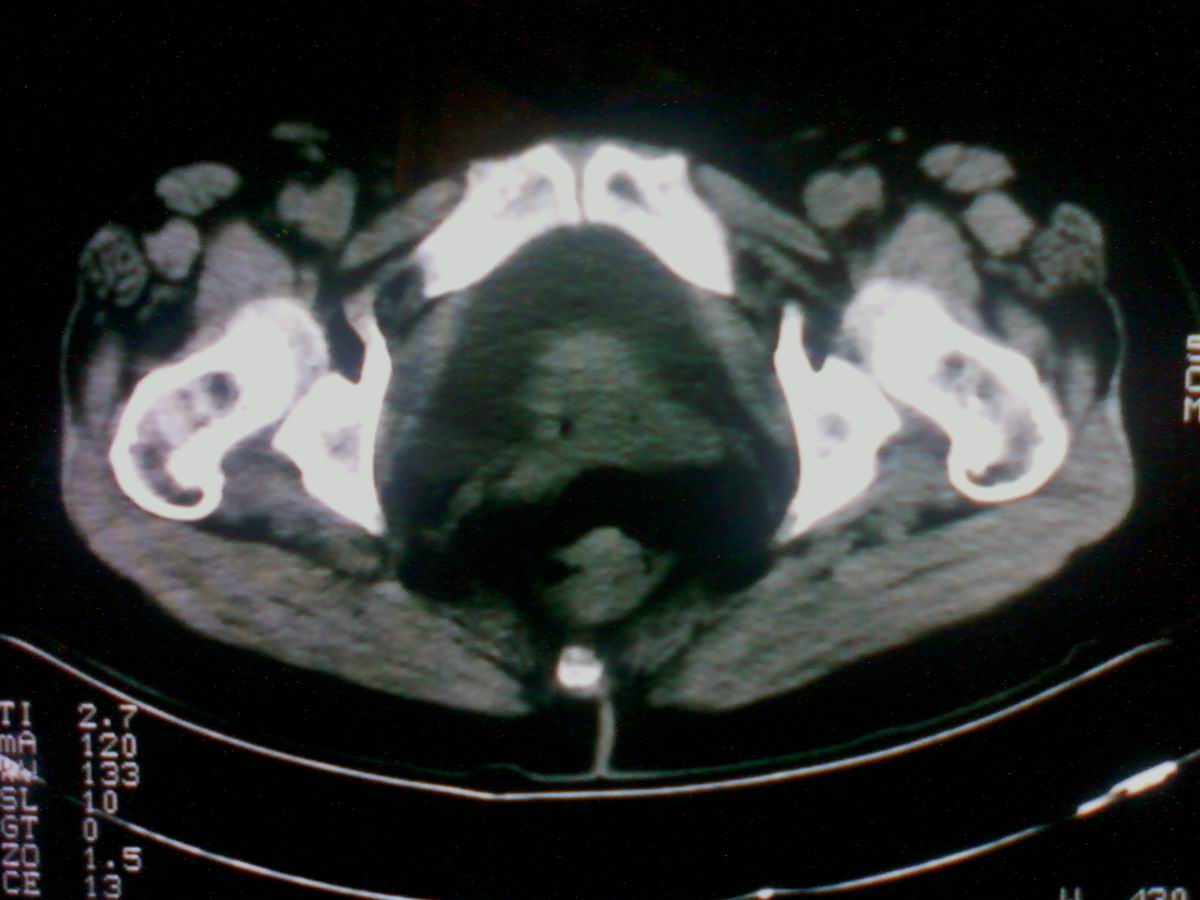

标题: CT25799:女性患者,45岁,腹胀,上腹部疼痛来诊,B超示盆腔 [打印本页]

标题: CT25799:女性患者,45岁,腹胀,上腹部疼痛来诊,B超示盆腔

考虑卵巢癌伴腹水

1)考虑卵巢恶性肿瘤。2)腹水。